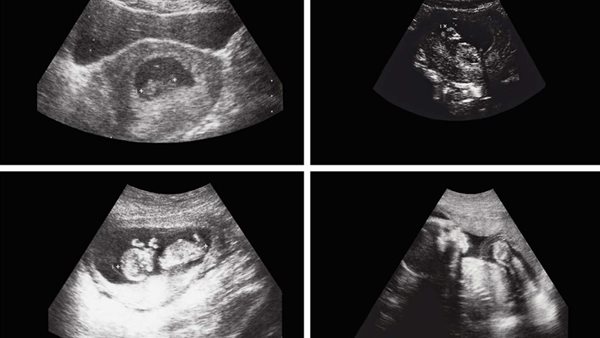

ووفقًا لصحيفة ذا ميرور، استقبل المستشفى الرضيع بعد ملاحظة انتفاخ غير طبيعي في بطنه، وفي البداية اشتبه الأطباء في إصابته بورم كلوي، إلا أن الفحوصات بالأشعة كشفت عن وجود تكوين داخل تجويف البطن يحتوي على أنسجة رخوة، ودهون، وسوائل، بالإضافة إلى هيكل عظمي واضح، ما أثار الشكوك حول احتمالية وجود جنين داخل جسمه.

وبعد التأكد من التشخيص، أجرى الفريق الطبي عملية جراحية دقيقة استغرقت عدة ساعات، تمكنوا خلالها من استخراج الجنين الذي بلغ حجمه حوالي 8×12 سنتيمترًا، وأشرف على الجراحة مجموعة من الجراحين الأفغان المتخصصين.